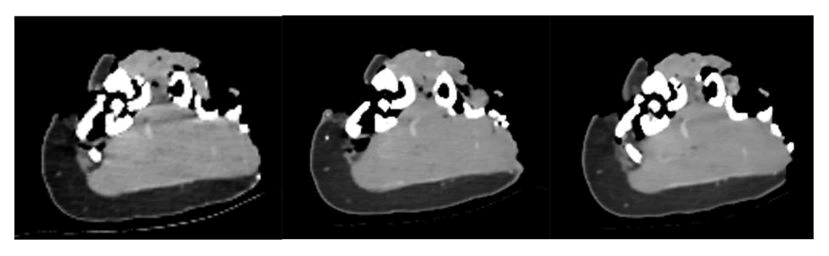

In Figure 8, we move to the lower limbs. In this case, there are metallic foreign bodies that increase the level of artifacts in the image. With the acquisition at 80 KV, the artifacts are widespread and may affect the correct identification and numbering of the number of lesions and/or fragments. With the scan at 120 KV, there is an improvement in image quality with the reduction of artifacts but a consequent flattening of the image. Once again, fused CT represents the best compromise to have all the relevant elements for the case in a single image.

XXXXXXXX

Figure 8. Comparison of images of the left leg reconstructed with fused CT and acquisitions at different energies: Respectively 80 KV (on the left), 120 KV (in the center) and fused CT (on the right).